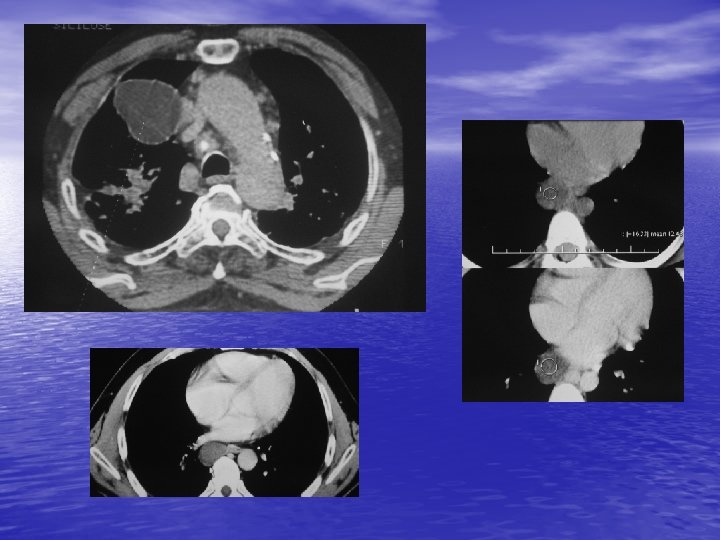

3. MASSES DU MEDIASTIN ANTERIEUR 3. 1. Tumeurs thymiques - Environ 50 % des masses non ganglionnaires et vasculaires. - Tumeurs les plus fréquentes du médiastin antérieur. - 50 % asymptomatiques, myasthénie. - Bénin ou malin : souvent pas de différenciation par l’imagerie.

3. 2. Autres tumeurs - Tumeurs germinales (tératome, carcinome embryonnaire). - Adénome parathyroïdien. - Lymphangiome kystique. - Kyste pleuro-péricardique. - Goitre plongeant. - Pseudo tumeur graisseuse (par hernie diaphragmatique antérieure), vasculaire (anévrysme de l’aorte ascendante ++), cardiaque.